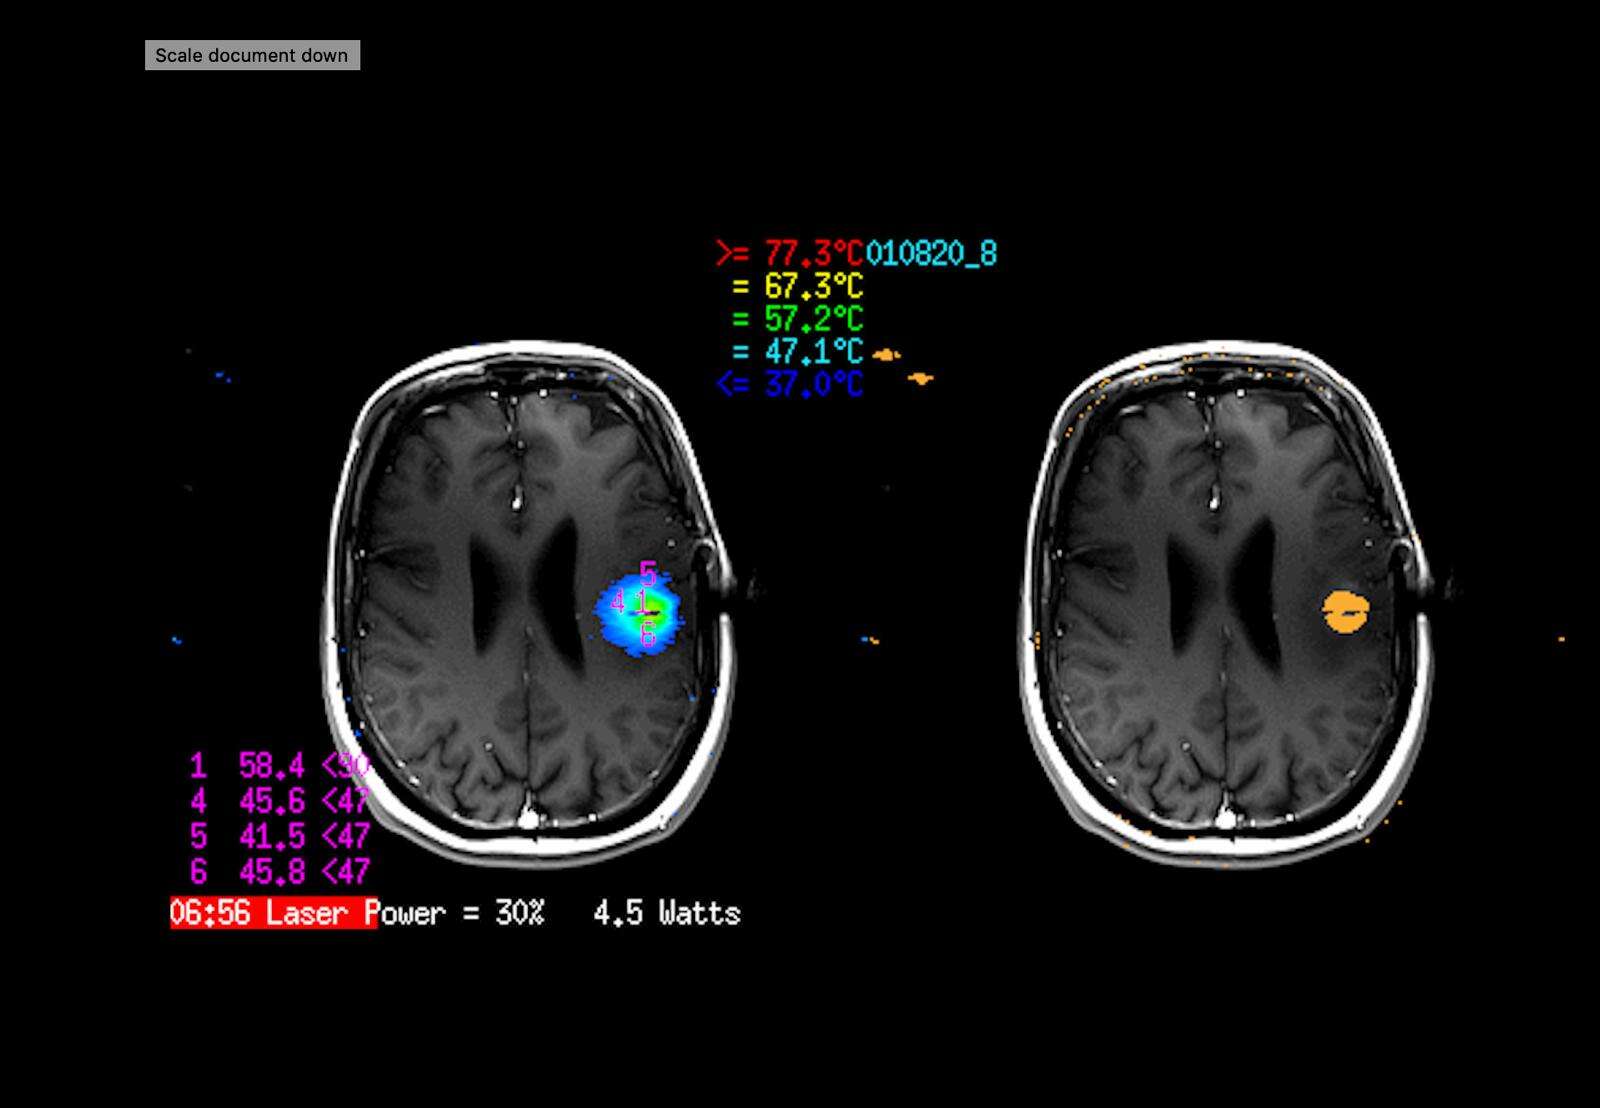

"טכנולוגיית הלייזר החדשנית מאפשרת צריבה בלייזר של מוקדים בעומק המוח, בגישה זעיר פולשנית דרך חור קידוח זעיר של מספר מ״מ בגולגולת. ההליך מבוצע באמצעות טכנולוגיה הנקראת Laser interstitial thermal therapy (LITT) בעזרת מכשיר ה-Visualase™ של חברת מדטרוניק. הפעולה הטיפולית משלבת בין טכנולוגיות לייזר זעיר פולשנית וסריקת MRI מתקדמת, המאפשרת בקרה בזמן אמת של גודל האזור הנצרב במוח, תוך בקרה מדויקת של עליית הטמפרטורה בגידול המביאה להשמדתו.

תהליך הטיפול כולל בשלב הראשון השתלת סיב אופטי עדין בצורה מדויקת למרכז הגידול בחדר ניתוח באמצעות מערכת ניווט מיוחדת ודרך חור קידוח זעיר בגולגולת בקוטר של כ-3 מ"מ. בשלב השני המתבצע במכשיר ה-MRI, מחובר הסיב האופטי למערכת ה-Visualase™.

הצריבה עצמה מתבצעת כאשר המטופל מורדם בתוך מכשיר ה-MRI תוך ניטור מתמשך בזמן אמת של שינויי הטמפרטורה במוח, ובקרה קפדנית על גודל האזור הנצרב. בצורה זו ניתן לשמור על אזורים מוחיים סמוכים לאזור הצריבה היכולים להיות אחראים על תפקודים קריטיים", מסביר ד"ר שטראוס.